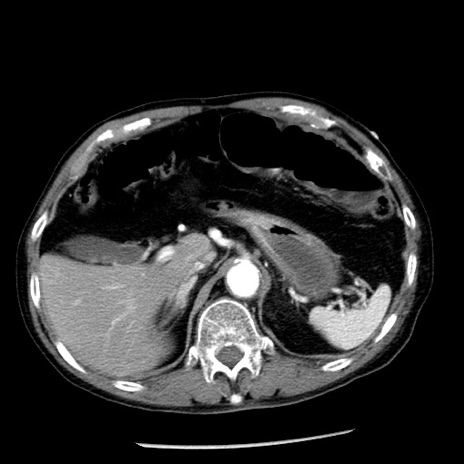

冠状断像